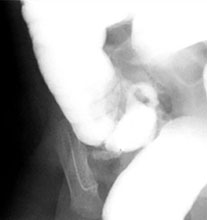

Intussusception

is the telescoping of one portion of the bowel into another. For example,

the terminal ileum could invaginate into the colon. Idiopathic incidences

may be seen following viral illness with hypertophy of Peyer's patches

in the terminal ileum. Age of presentation is usually 3 months to 24 months.

Pathologic intussusception is associated with a lead point such as a tumor, inspissated feces (cystic fibrosis) or lymphoma, often in older child greater than age 2. Symptoms include crampy abdominal pain, bloody stools, and vomiting. Treatment is fluoroscopically

guided reduction with air or fluid enema or surgery if unreducible. At our institution an air enema is first performed followed by surgery if this method is unsuccessful. |